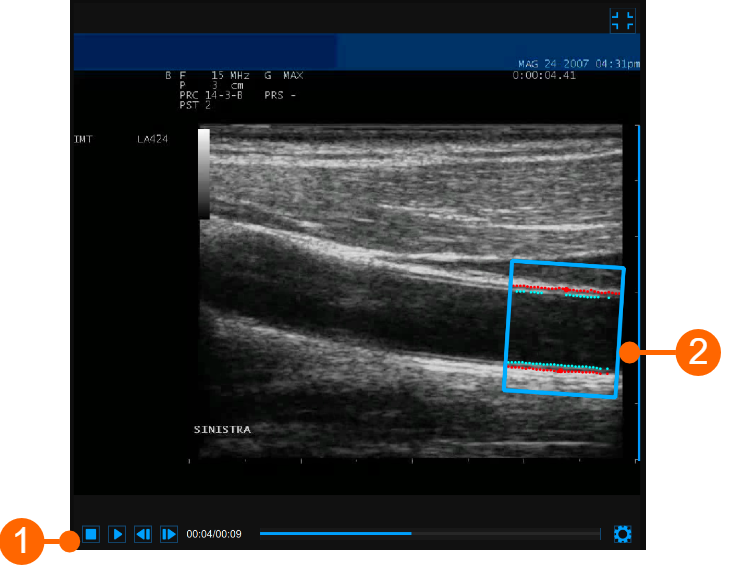

Video window

The video window shows the video signal from your ultrasound system. The points of the Lumen-Intima interface and the Media-Adventitia interface are displayed within the ROI (2) in cyan color.

The video control bar (1) is located at the bottom of the window.

If you want to expand the video window, you have to click on the Enlarge button.